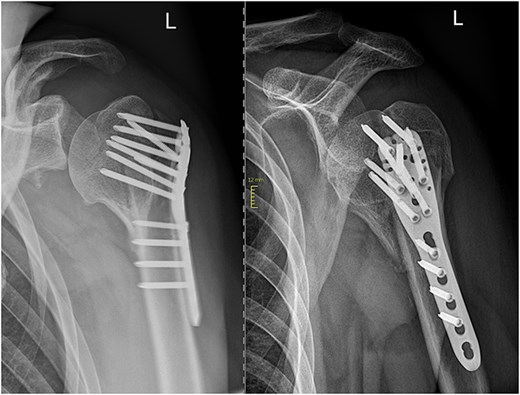

The initial postoperative therapy proceeded without complications and the patient was able to perform initial pendulum exercises under physiotherapeutically guidance. In the postoperative radiographic assessment of the fracture fragments exhibited an anatomically aligned position. However, it also showed a slight widening of the subacromial space. Antiepileptic therapy was again reviewed and adjusted in consultation with a neurologist to minimize the risk of future seizures.

In subsequent clinical and radiological follow-ups at 2, 6, and 24 weeks postoperative, the humeral head depression showed regression, and the patient was able to progressively increase joint demands (Fig. 3). Training under physiotherapeutic supervision was difficult because of his secondary diagnoses. In the end after 6 Months he was unaffected in his daily living and painless.